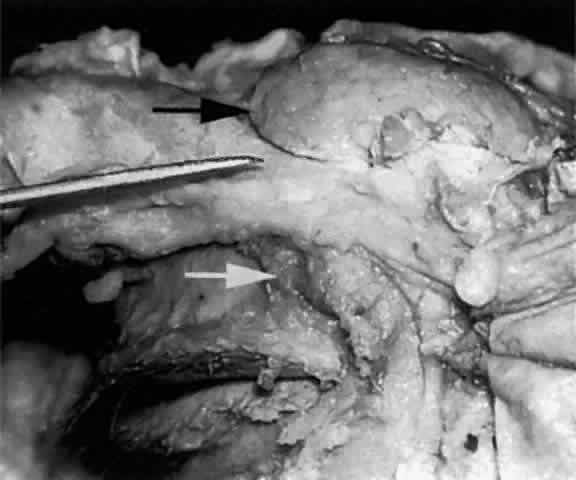

Fig. 2. With the roof and lateral wall of the left orbit removed, this cadaver dissection demonstrates the orbital lobe (black arrow) and the palpebral lobe (white arrow) separated by the lateral horn of the levator aponeurosis (pointer).

The almond-shaped orbital lobe (see Fig. 2) represents approximately 65% to 75% of the gland and measures 20 mm long × 5 mm thick × 12 mm wide.2 Its sharp anterior border rests behind the superior orbital rim and is covered by the orbital septum (Fig. 4) and a portion of the temporal aspect of the central preaponeurotic fat pad (Fig. 5). Posteriorly, its rounded border is supported by a large superotemporal fat pad at the plane of the posterior pole of the globe.3 The convex superior surface is suspended from the periorbita of the lacrimal gland fossa of the frontal bone. The inferior border is convex and attached to the sheath of the levator aponeurosis. Its lateral border is smooth and convex in contour with the bony fossa.

The inferior or palpebral lobe of the lacrimal gland (see Fig. 2) represents approximately 25% to 35% of the gland and lies beneath the levator aponeurosis in the subaponeurotic space. It extends anteriorly beyond the orbital margin to lie in the lateral portion of the superior fornix. The palpebral lobe can be seen through the conjunctiva when the eyelid is elevated or everted (Fig. 6).